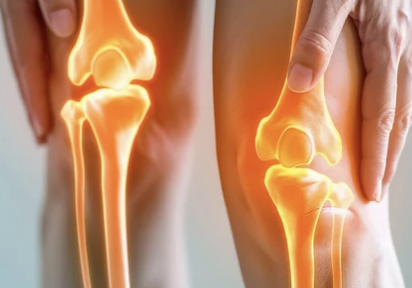

무릎 연골 손상은 초기에는 특별한 증상이 없을 수도 있지만, 점차 진행되면 다음과 같은 증상이 나타날 수 있어요.

- 무릎 통증: 계단을 오르내리거나 쪼그려 앉을 때 무릎 앞쪽이나 안쪽에서 통증이 느껴질 수 있어요.

- 무릎 부종: 연골 손상으로 인해 무릎 관절에 염증이 생기면 무릎이 붓고 열감이 느껴질 수 있어요.

- 무릎 뻣뻣함: 무릎 관절이 뻣뻣하게 느껴지고 움직임이 불편할 수 있어요. 특히 아침에 일어났을 때 뻣뻣함이 심할 수 있어요.

- 무릎에서 소리: 무릎을 움직일 때 뚝뚝, 덜컹덜컹 하는 소리가 나거나 걸리는 느낌이 들 수 있어요.

- 무릎 불안정성: 무릎이 힘없이 꺾이거나 휘청거리는 느낌이 들 수 있어요.